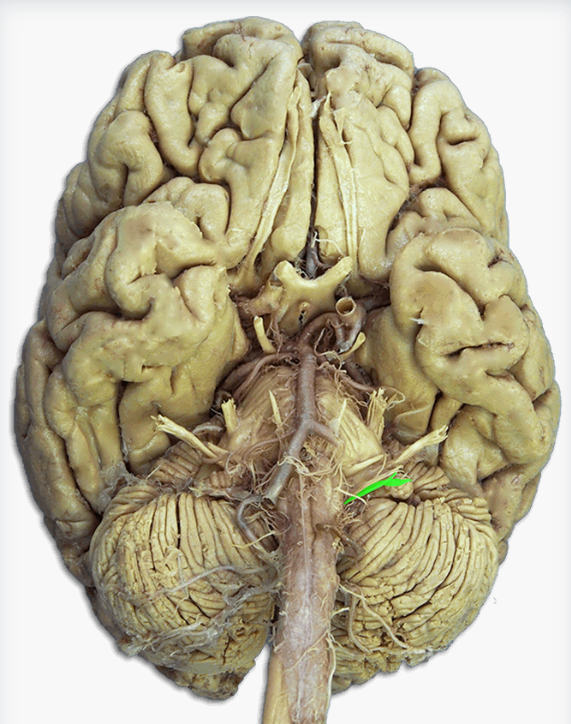

Label this cranial nerve

Olfactory (CN I) nerve

Label this cranial nerve

Optic (CN II) nerve

Label this cranial nerve

Oculomotor (CN III) nerve

Label this cranial nerve

Trochlear (CN IV) nerve

Label this cranial nerve

Trigeminal (CN V) nerve

Label this cranial nerve

Abducens (CN VI) nerve

Label this cranial nerve

Facial (CN VII) nerve

Label this cranial nerve

Vestibulocochlear (VIII) nerve

Label this cranial nerve

Glossopharyngeal (CN IX) nerve

Label this cranial nerve

Vagus (CN X) nerve

Label this cranial nerve

Accessory (CN XI) nerve

Label this cranial nerve

Hypoglossal (CN XII) nerve